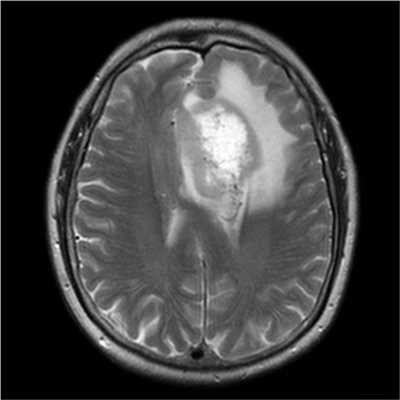

МРТ головного мозга. Т2-взвешенная аксиальная томограмма. Арахноидальная киста. Цветовая обработка изображения.

Арахноидальные кисты представляют собой скопление ликвора между листками расщепленной паутинной оболочки. Арахноидальная киста обычно не сопровождается другими мальформациями. Незначительная часть арахноидальных кист имеет приобретенное происхождение - следствие лептоменингита, операции или кровоизлияния. Частота составляет около 1% от внутричерепных образований. Соотношение полов М:Ж, как 4:1. Типичная локализация - средняя черепная ямка (в области Сильвиевой борозды 50%), межполушарная щель, мосто-мозжечковый угол (11%), за скатом или на уровне четверохолмия (10%), в области червя мозжечка (9%), реже в области межножковой и предмостовой цистерн (3%), а также супраселлярной и хиазмальной цистерн. Ретроцеребеллярная арахноидальная киста довольно часто встречаются за мозжечком и отличима от mega cisterna только по неизменённой задней черепной ямке. Содержимое кисты чисто ликворное, стенки гладкие, чётко очерченные, внутри кисты могут быть перегородки. Мелкие арахноидальные кисты очень трудно увидеть. Меняя ширину окна и его уровень на Т1-взвешенных МРТ изображениях можно заметить, что киста чуть светлее ликвора. Дифференциальная диагностика с эпидермальными кистами лучше осуществляется с помощью МРТ последовательности FLAIR. Эпидермальные кисты становятся яркими, в отличие от гипоинтенсивных арахноидальных.